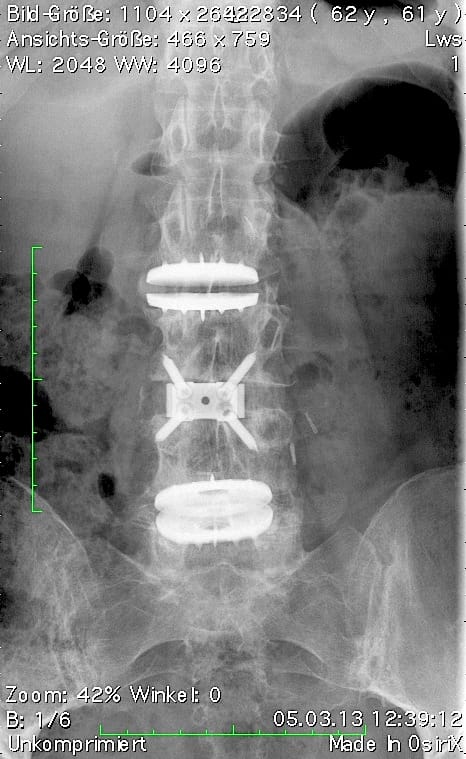

Compared to other implants, the viscoelastic disc prosthesis has the advantage that its design perfectly mimics the function of the natural disc. Furthermore, extensive laboratory testing has proven that it has a durability of at least 50 years. Whether and how surgical treatment of the affected vertebral segments should be carried out is planned individually by the specialist after thorough diagnosis (MRI, CT, X-ray, physical and neurological examination). If, for certain reasons, partial fusion of a section of the spine is unavoidable, this should be limited to one segment as far as possible, as shown in the following example. In this way, the greatest possible functionality of the spine can be maintained or restored.

Postoperative status: Complete axial correction of the lumbar spine with two disc prostheses and a PEEK cage. Normal lordosis of the lumbar spine also visible in the lateral view after the operation. (Spine Centre Rischke)

(2) Example of treatment with a viscoelastic disc prosthesis and dynamic fixator in the presence of spondylolisthesis